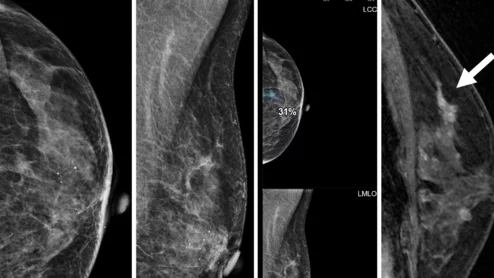

Thanks to AI, clinicians can use mammograms to do a lot more than identify signs of breast cancer. Researchers explored data from nearly 50,000 patients, presenting their findings in Heart.